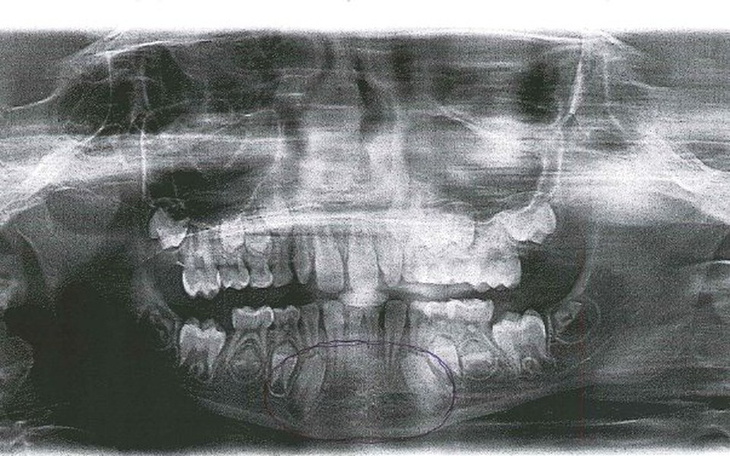

Jestem ojcem córki u której nie pojawiły się zalążki zębów stałych i gdy mleczaki wypadły została przerwa, są to dwie jedynki. pomoc jaka zostanie zaoferowana będzie wykorzystana na założenie aparatu na zębnego do dostosowania miejsca na protezę stomatologiczną.